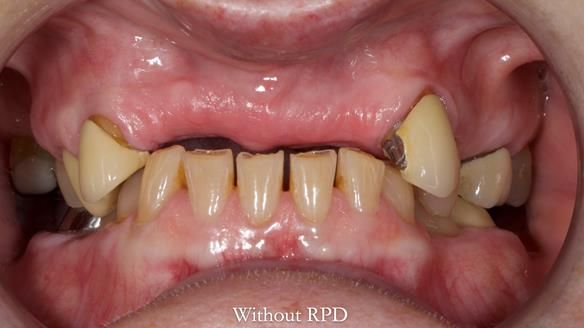

This is one of those cases that reminds me why I love removable prosthodontics. Pam was an absolute joy to treat — we were on the same page throughout. Her old upper flexible denture was loose, uncomfortable, and unaesthetic. We replaced it with a carefully designed metal-based upper partial denture/splint and new porcelain-bonded-to-zirconia (PBZ) crowns for the canines. The result is stable, comfortable, and natural-looking.

- Diagnosis and plan – Flexible upper denture ill-fitting with poor stability, retention, and appearance. Plan: metal-based upper partial denture/splint with lighter porcelain-bonded-to-zirconia crowns on UR3 and UL3.

- Better support for lips and lower face.

- Natural smile and improved chewing.

- Designed to protect remaining teeth.